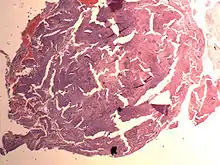

Endometrial Stromal Nodule

An endometrial stromal nodule is a noninfiltrative, circumscribed proliferation of endometrial stromal cells and is a benign subtype of endometrial stromal tumor. The appearance of the cells is identical to normal endometrial stromal cells. This can only be differentiated from low-grade endometrial stromal sarcoma by confirming lack of infiltration.

The differential includes cellular leiomyoma. Diagnosis may be aided by immunostaining; endometrial stromal nodules are positive for CD10; leiomyomas are positive for caldesmon and desmin (and sometimes CD10).